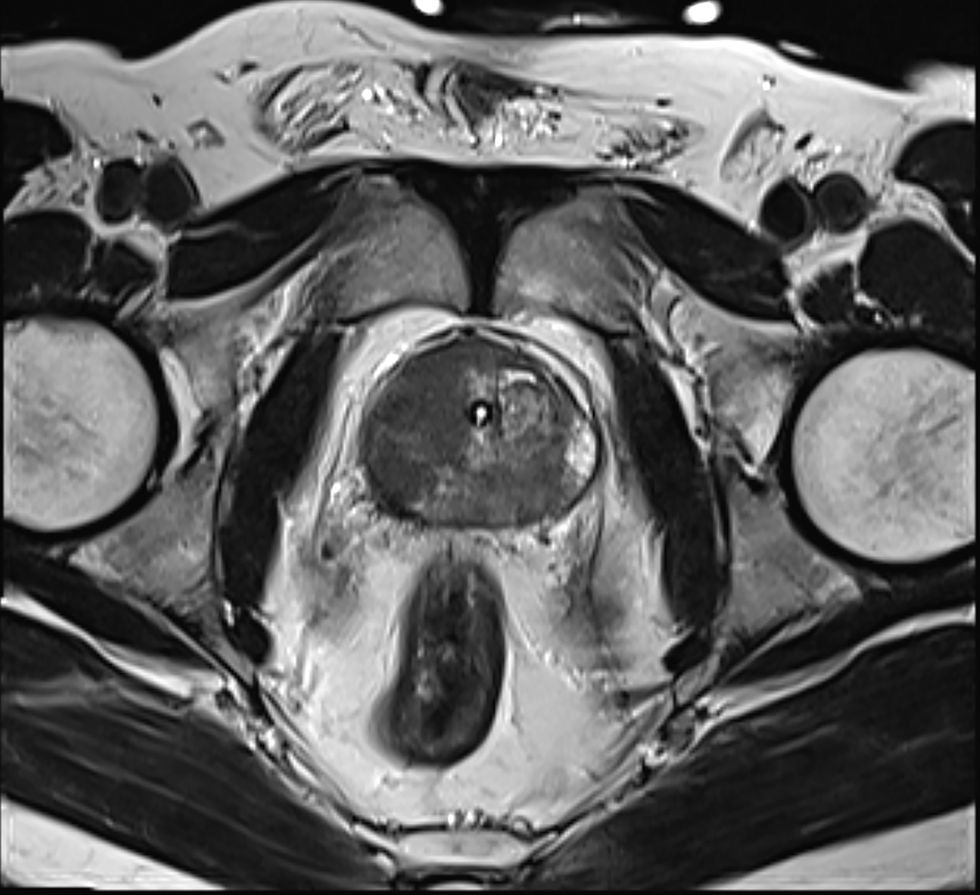

If results raise concerns, patients may be referred for an MRI scan to get detailed images of the prostate, followed by a biopsy if anything suspicious appears.